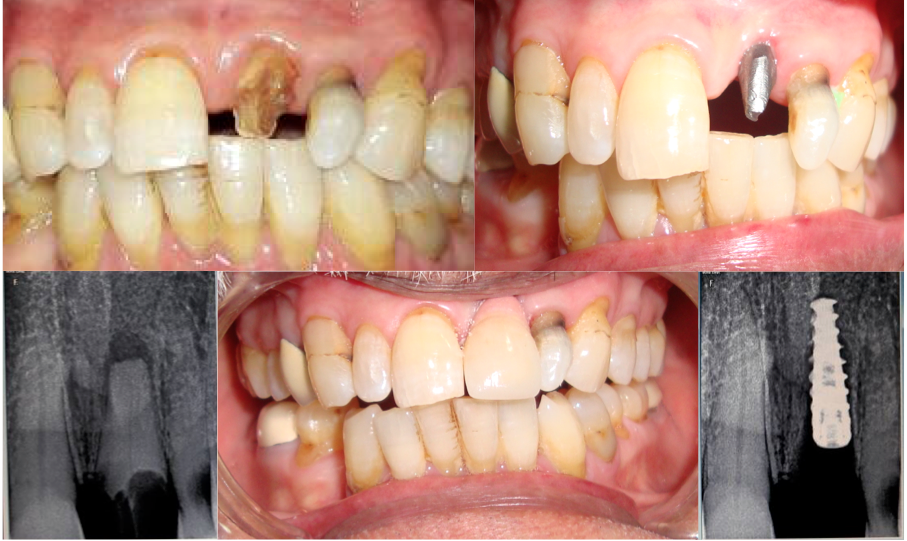

Oro - dental Surgery

This section includes Surgical procedures required to correct and teat minor oral diseases like abnormal growths and also removable of unpacked teeth from undesirable positions

Extraction of teeth, Alueoloplasty, Frenectomies, mucosal lesions bioply dental implants and other procedures.